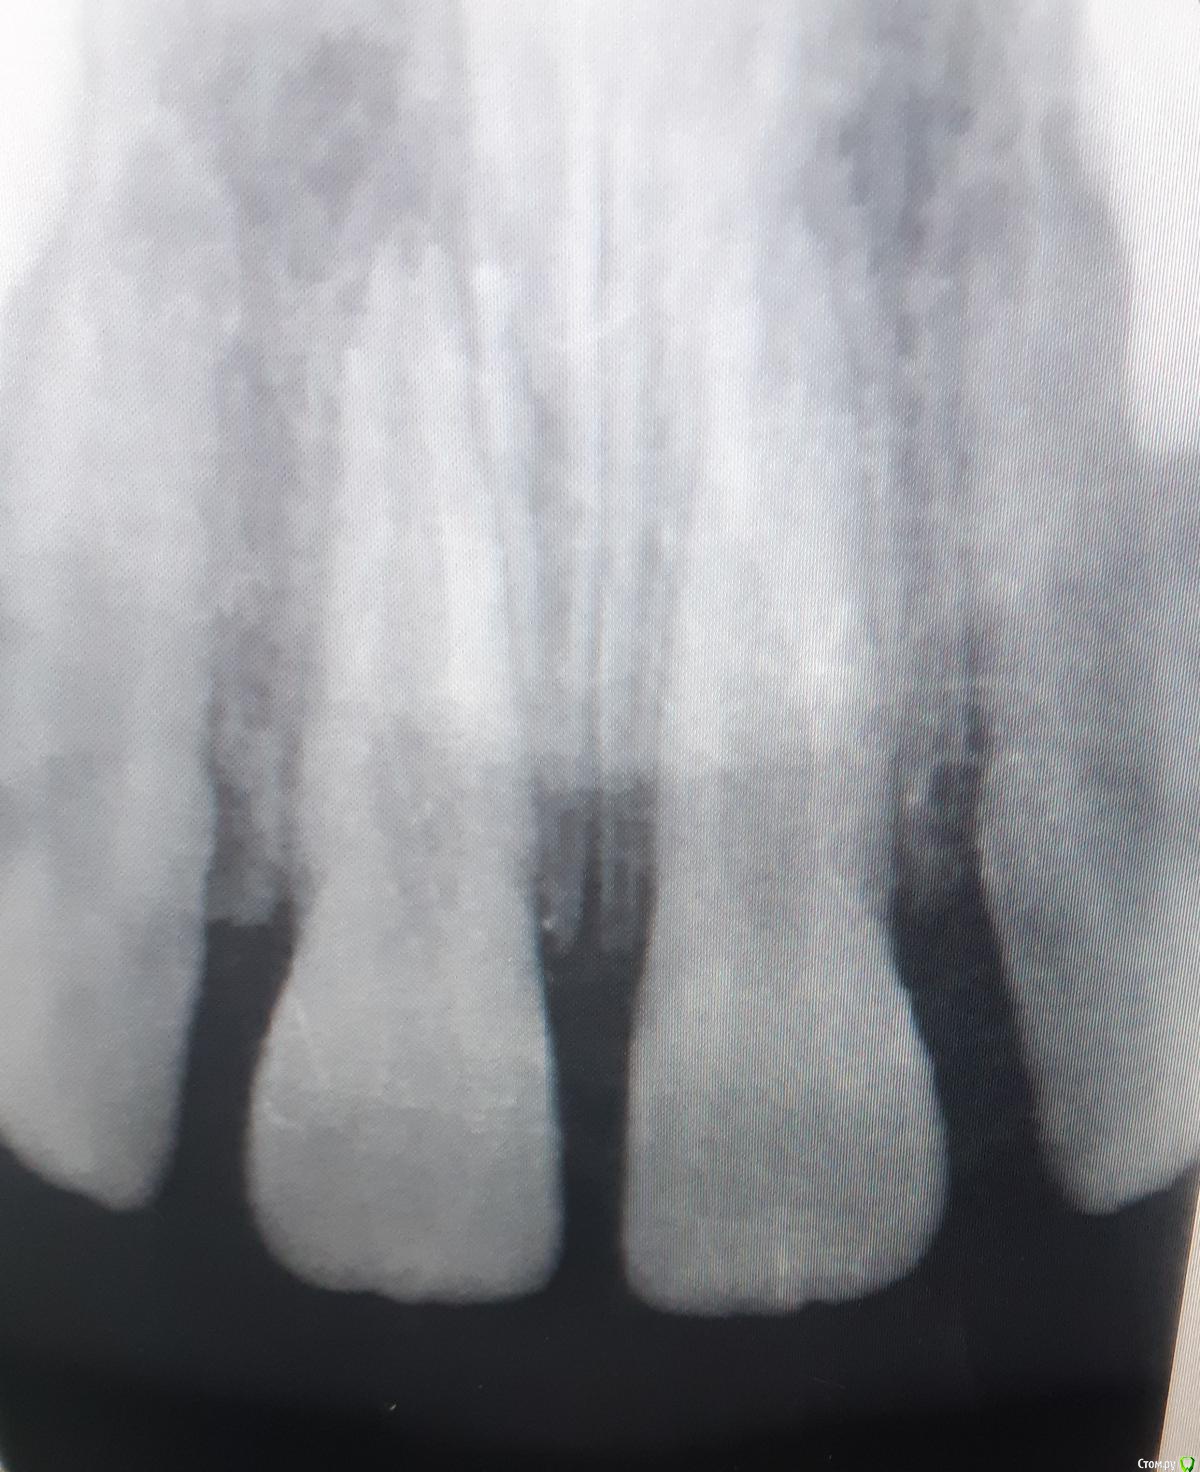

ANCHOUSE Опубликовано 30 марта, 2019 Автор Поделиться Опубликовано 30 марта, 2019 Сделали ктhttps://yadi.sk/d/W9n5FOqj7Rpb4A Ссылка на комментарий

ANCHOUSE Опубликовано 30 марта, 2019 Автор Поделиться Опубликовано 30 марта, 2019 Почему нет кортикалки между 21 и резцовым каналом? Ссылка на комментарий

kramer Опубликовано 30 марта, 2019 Поделиться Опубликовано 30 марта, 2019 Мне кажется, кость рассосалась вследствие возникновения этого новообразования. 1 Ссылка на комментарий